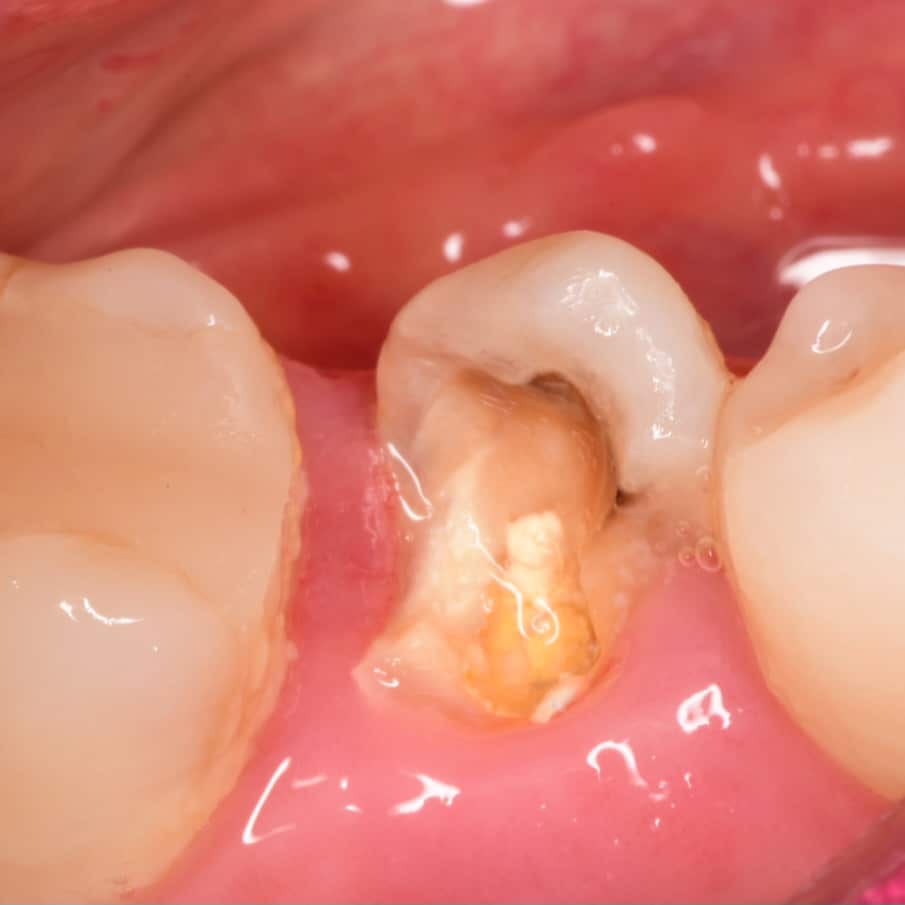

Initial situation showing badly carious lower second premolar

Buccal view showing the same destruction of the tooth, the patient insisted on restoring her tooth

Isolation, look to the amount of tooth structure left under the gingival tissue, dentin quality looks good for bonding, so lets go with adhesive dentistry